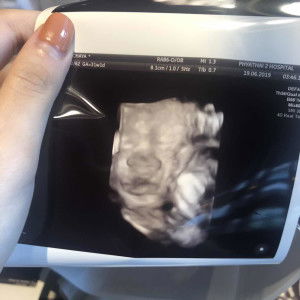

วิธีเพิ่มน้ำคร่ำ

วันนี้ไปซาว4มิติมาค่ะพบว่ามีภาวะน้ำคร่ำน้อยกว่าปกติ คุณหมอบอกว่าต้องพยายามเพิ่มน้ำคร่ำแต่ไม่ได้บอกวิธีมาค่ะ เลยอยากสอบถามว่าคุณแม่ท่านไหนพอทราบวิธีบ้างคะ ตอนนี้31สัปดาห์ค่ะ